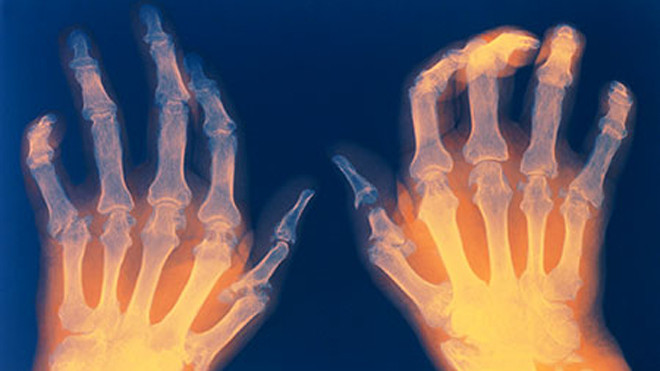

Bàn tay biến dạng do viêm khớp dạng thấp